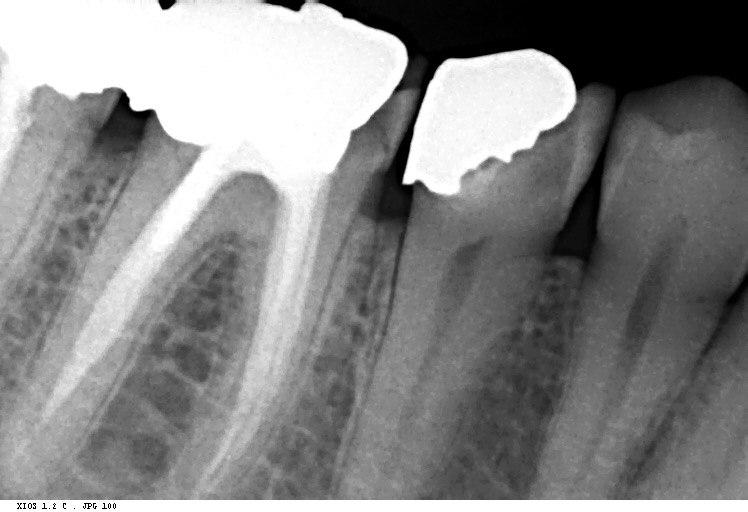

Question2: Which surface shows overhang?